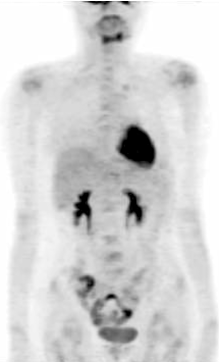

张国淳:该患者至我院治疗时局部复发及骨转移与内脏转移并存, 肿瘤负荷大, 应该考虑首选联合化疗。对于在辅助治疗中使用过蒽环类的患者, 复发转移后的一线治疗方案可以选择多烯紫杉醇联合卡培他滨(XT方案), 该方案的总有效率高于40%。该方案同时也是NCCN乳腺癌临床指引及AGO乳腺癌临床指引所强烈推荐的。因此, 我们在患者的一线治疗中采用了XT每3周方案。然而, 在化疗2个周期后我们又进行了一次PET的疗效评价, 结果显示:右侧乳腺、双肺多发结节、肝脏肿块、盆腔淋巴结及全身多处骨髓局灶性葡萄糖代谢异常增高灶, SUV较前明显降低; 与前一次本院PET影像比较, 可见新发病灶(肝脏), 见图2。那么如何评价此时的疗效呢?是否需要更换二线化疗方案?